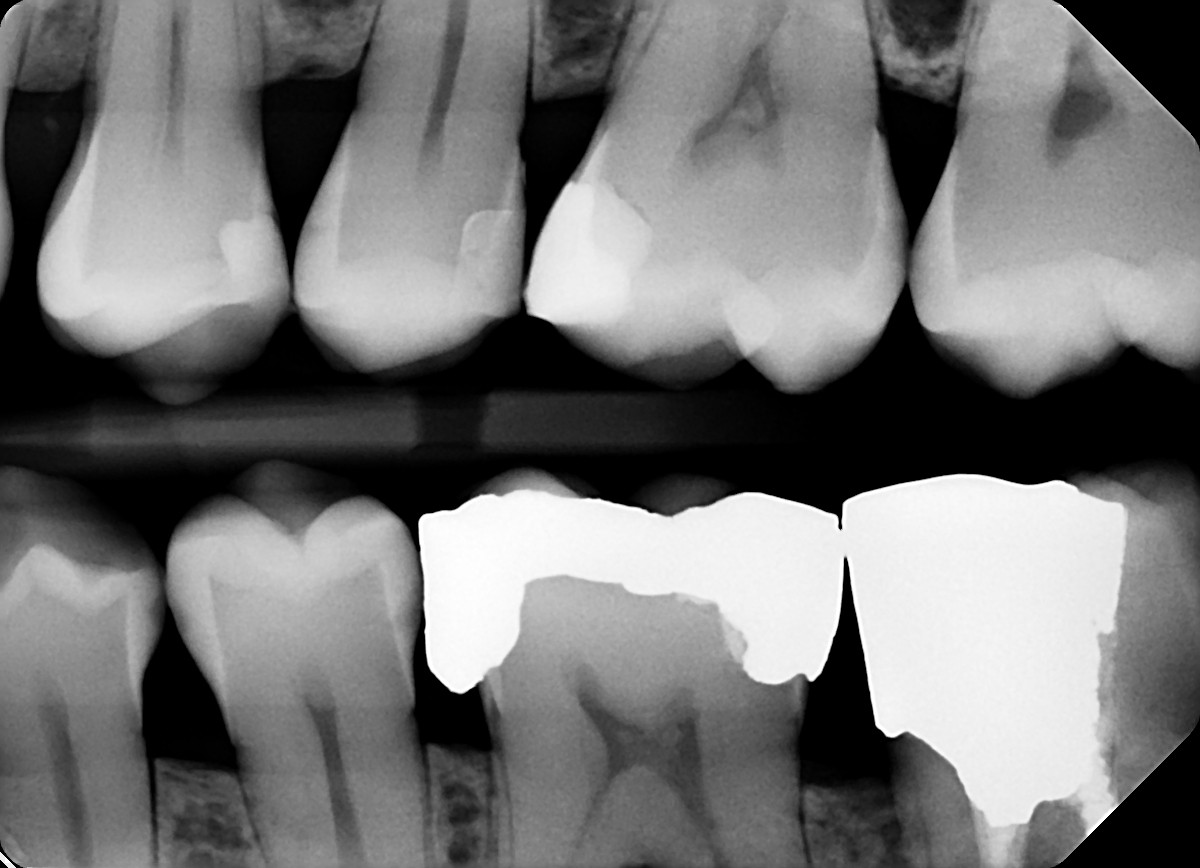

10 / 35

10. On which surface a recurrent caries can be detected?

Dital tooth # 4.6 although defective there is no recurrent caries, tooth # 1.4 shows overlay